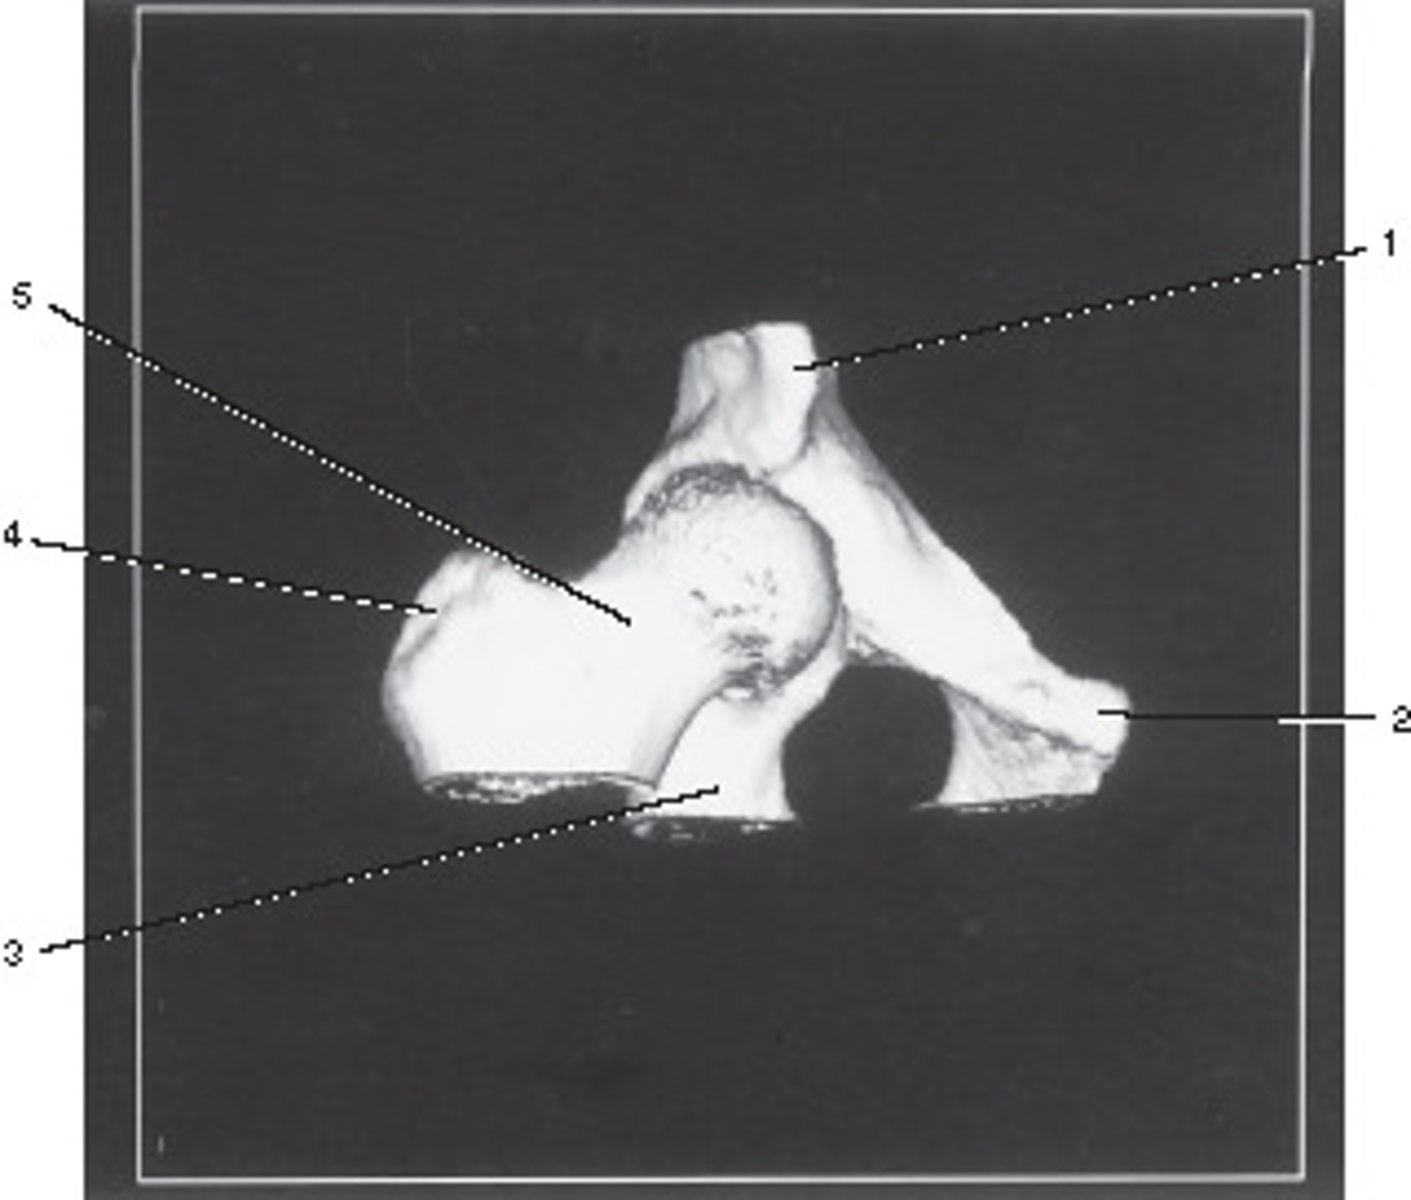

Oblique Axial Plane

This anatomic plane can best be described as the:

<p>This anatomic plane can best be described as the:</p>

Fovea Capitis

Number 1 corresponds to which of the following?

<p>Number 1 corresponds to which of the following?</p>

Talus

Number 2 corresponds to which of the following?

<p>Number 2 corresponds to which of the following?</p>

Fibula

Sesamoid Bones